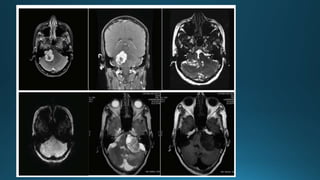

Cerebellopontine angle tumours